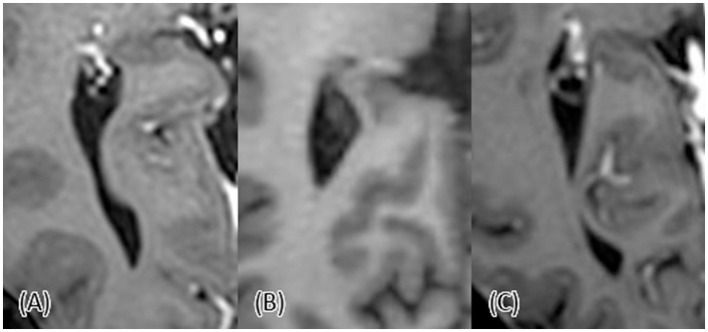

Introduction: Anatomical variations in the posterior horns of the lateral ventricles are well-documented, with the horn presenting as open, constricted, or completely closed. However, the extent and nature of these variations across different demographics remain under-explored. This study aimed to investigate the anatomical variations of the posterior horn of the lateral ventricles across different age and sex groups and to compare the variations between the right and left sides.

Methods: We conducted a retrospective analysis of magnetic resonance imaging (MRI) scans from 217 adult participants across 15 age groups, utilizing a stratified random sampling from a radiology database. MRI scans were analyzed for ventricular dimensions, and horn types (open, constricted, and closed). Statistical significance was defined as p-value < 0.05.

Results: Variants of the posterior horn were observed frequently, with open posterior horn being the most common in the left lateral ventricle (41%) and constricted type being the most common in the right lateral ventricle (37%). A significant correlation existed between the right and left horn types, but in most cases, there was a difference in type between the right and the left horns in the same individual. No significant association between age and the type of the posterior horns was found. However, there was a significant difference in the width and length of the horns between the open and other types, with open horns being wider and longer. Lastly, the left horn appeared longer than the right one.